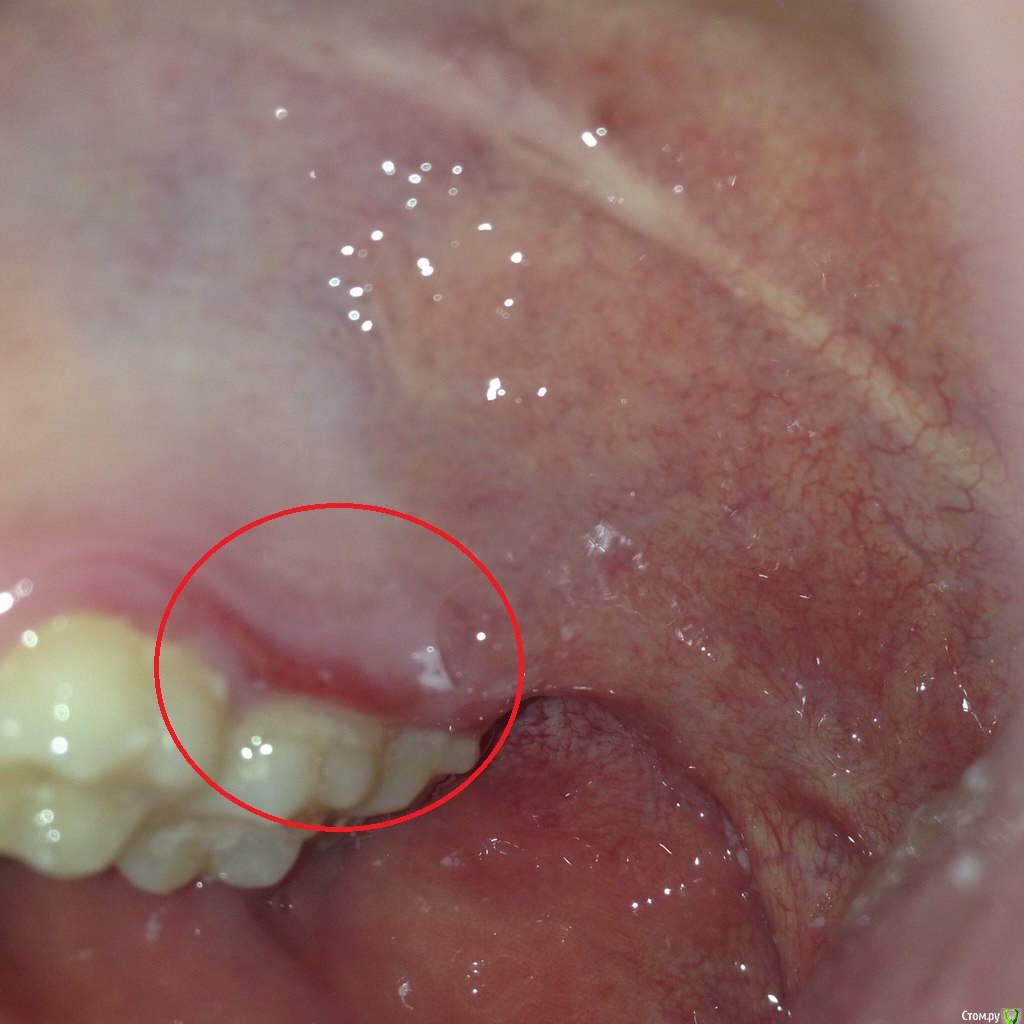

impreZe Опубликовано 26 августа, 2015 Поделиться Опубликовано 26 августа, 2015 (изменено) Доброго времени суток!23.08.15 съел кусок горячего шашлыка (прямо с мангала), после чего почувствовал дискомфорт в районе верхней десны (ранее такого не было), обнаружил тонкую красную полоску, сейчас она теряет цвет.Не подскажите, ожог ли это или мне идти к стоматологу? Изменено 26 августа, 2015 пользователем impreZe Ссылка на комментарий

shishok Опубликовано 26 августа, 2015 Поделиться Опубликовано 26 августа, 2015 Можно и к стоматологу сходить для успокоения,но обычно ожоги слизистой заживают за 2-3 дня сами. Ссылка на комментарий

shishok Опубликовано 26 августа, 2015 Поделиться Опубликовано 26 августа, 2015 Постарайтесь первые дни ограничить приём горячей пищи,острого,солёного. Ссылка на комментарий